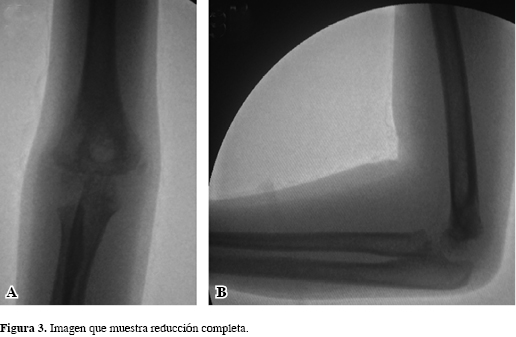

Se trata de una niña de cinco años de edad, previamente sana y sin antecedentes quirúrgicos ni traumáticos de ningún tipo, quien cayó desde una altura de 1.5 m, recibiendo un trauma directo en el miembro superior derecho con el codo en flexión y contusión por el cuerpo con posterior edema dolor y deformidad del codo derecho. Consultó al Servicio de Urgencias de nuestro hospital, presentando al ingreso edema en la región del codo derecho con equimosis localizada, deformidad y dolor sin déficit neurovascular distal. Se tomaron radiografías (Figura 1 A-C), donde se observó una luxación del codo derecho asociado con fractura del epicóndilo lateral. Consideramos realizar un manejo quirúrgico, con reducción cerrada fijación percutánea con clavos de Kirschner (Figura 2 A y B), llevada a cabo sin complicaciones (Figura 3). La paciente egresó con plan de fisioterapia y seguimiento con controles periódicos y al cabo de dos meses se encontró con resultados satisfactorios, con rangos de movilidad conservados con ligero cúbito en varo de 14 grados, el cual ha venido mejorando. Por todo lo anterior, consideramos que es un resultado postoperatorio satisfactorio con buenos resultados funcionales (Figuras 4 y 5).

El tratamiento de la fractura de epicóndilo lateral sin luxación del codo es controversial;3 en cuanto a los tipo I y II, algunos autores respaldan el manejo no quirúrgico.3 La mayoría de estudios coinciden que el manejo de la luxofractura debe realizarse precozmente, realizando reducción cerrada de la luxación y posteriormente una reducción abierta por abordaje lateral y osteosíntesis con dos o tres clavos de Kirschner, dependiendo de los hallazgos intraoperatorios.1,2,3,9,11 Algunos hallazgos intraquirúrgicos son la no lesión de la cápsula posterior y el ligamento colateral, pero sí la tracción de los músculos extensores en el fragmento epicondíleo, produciendo estabilidad por parte de las estructuras blandas a la luxación; si se produce una lesión posterior de la cápsula sí condiciona inestabilidad.1,8 La reducción de la fractura debe ser anatómica debido a esta relación de tejidos blandos con la estabilidad articular, ya que la reducción ineficaz puede llevar a incongruencia articular llevando a pobres resultados funcionales.1,2,3